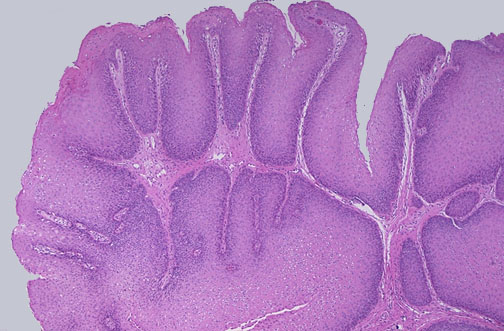

This is a squamous papilloma of the larynx, found on the true vocal fold. Note the long projections of squamous epithelium over fibrovascular cores. These uncommon lesions are solitary in adults, and may cause some bleeding.